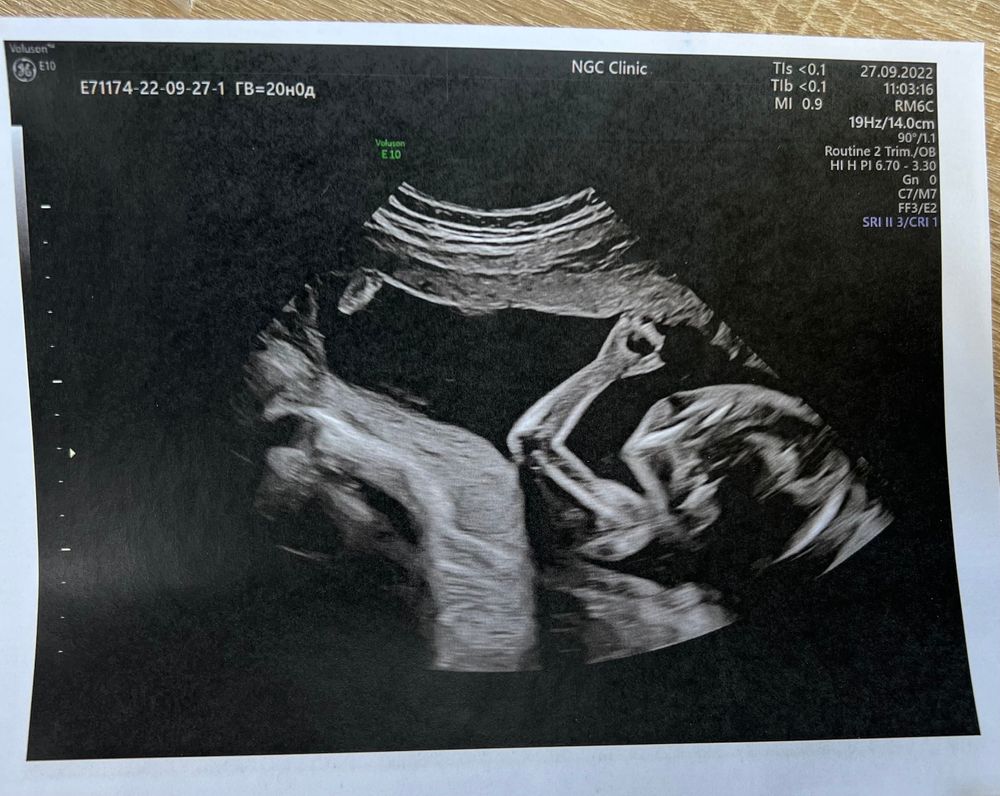

20 недель и второй скрининг

Jane, да, скромные девочки😁 а попинать - это они не скромничают🤷🏼‍♀️ моя сегодня лежала сначала правильно, но пока все замеры сняли, она отвернулась. И все, только затылок и ухо показала😁 и вам легко доходить и легко родить🤰🏼